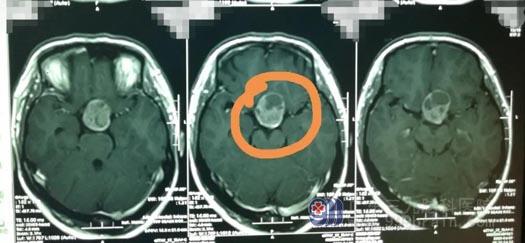

入院完善头颅CT检查后,鲁明发现她鞍区有巨大占位性病变。“根据影像检查结果,并且考虑到患者一直怀不上二胎、内分泌紊乱,所以初步认为是垂体瘤的可能性较大。”

肿瘤压迫并损害了视觉神经纤维,导致该患者出现头痛、双眼外侧偏盲和视力下降等症状。鲁明分析,如果继续放任不管,肿瘤会继续压迫大脑神经,进一步影响患者视力,甚至很可能会失明。

完善相关检查后,鲁明为患者实施了鞍区占位性病变切除术,成功切除了一个直径大小约5.0cm的瘤子。术后病理诊断为促肾上腺皮质激素细胞腺瘤。